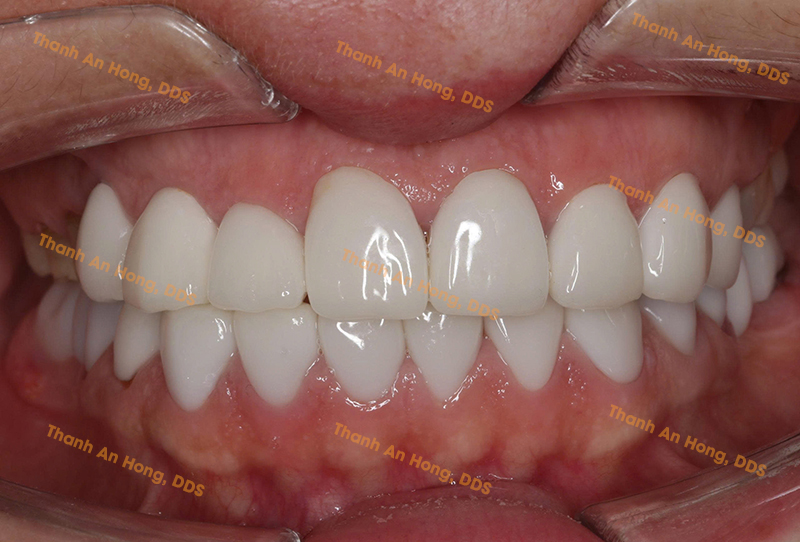

HÌNH ẢNH THỰC TẾ

Khay trong suốt chỉnh lệch đường giữa với toàn hàm là răng sứ